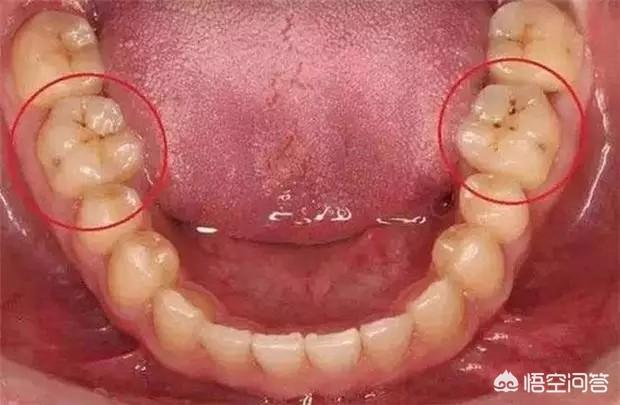

首先我们要了解牙齿的哪些部位容易产生蛀牙。容易产生蛀牙的地方按概率高低排列分别是牙齿的合面――邻接面――牙颈部――后牙的颊面沟以及前牙的舌面窝。

有时候我们看到一颗牙齿表面仅有一个黑点。平时只感觉冷、热、甜食刺激稍有些不适,并没有特别地疼痛过。可当牙医检查后告诉你这颗牙齿已经坏掉了之后你可千万别觉得诧异。往往外观只有一个小黑点而牙齿的内部已经腐坏不堪。

为什么会这样呢?很简单,外层牙釉质密度高呗!内层的牙本质密度相对较低更容易被侵蚀,因此蛀牙往往是外观看起来只有一点小问题,一个黑点或者一个小洞而内部却“豁然开朗”充满着腐败物质。